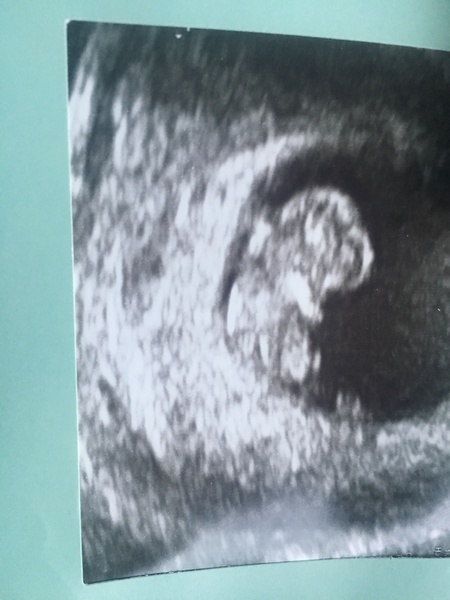

Karigan195 · 29/01/2019 09:03

Well got up with one of the worse ms mornings ever. Then went for the scan. Got to see the little heart beat and baby was jumping whilst the ultrasound was being done 😁

Measuring at 9 weeks 2 days. Will work out due date on that in a min 😁